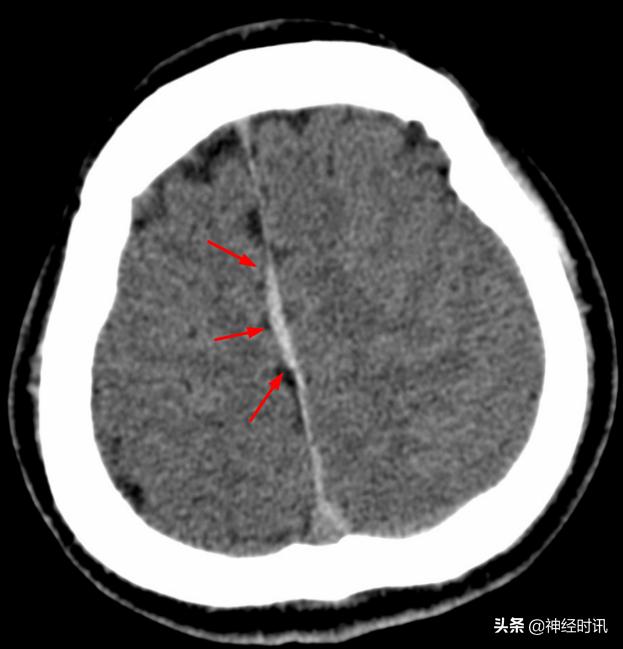

红箭所指的大脑镰局部呈连续的长条状高密度影,容易被误诊为少量蛛血,此系大脑镰局部不完全钙化所致。注意观察密度增高的大脑镰边缘非常光滑、且居中(红箭),与少量蛛血形成的偏密征、边缘毛糙等征象恰好相反。

间断性的大脑镰不完全线状钙化(红箭),同样呈边缘光滑、居中改变。